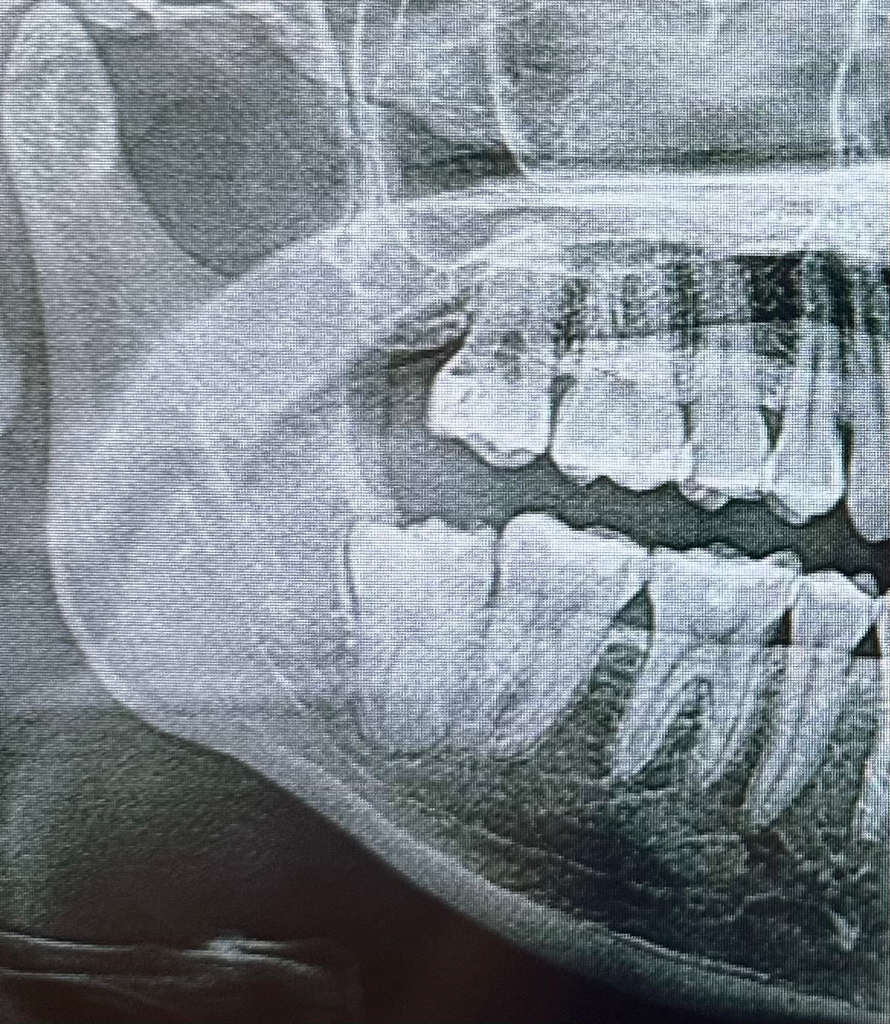

오른쪽 아래 부분매복 사랑니인데 최근에 잇몸위로 올라오면서 가끔 통증이 느껴집니다. 어금니랑 가까운것같은데 발치가 매우 어려운 케이스인가요? 일반치과가 아닌 대학병원에 가보는게 좋을까요?

• 1번 째 사진

사랑니의 뿌리가 신경과 인접해 있고 치아의 뒷면이 치조골에 뭍혀 있기 때문에 난이도는 상대적으로 높아 보입니다

일반치과에서 발치를 할수도 있지만 구강악안면외과 전문의가 있는 치과에서 발치를 하는것이 좋을 수 있급니디

난이도 자체는 크게 어려워 보이진 않지만 엑스레이 상으로 보면 사랑니가 약간 신경을 누르고 잇는것같습니다.

발치난이도는 사랑니가 잇몸뼈에 얼마나 파묻혀 있는지, 치아 뿌리의 모양은 어떤지, 옆 어금니와 얼마나 겹쳐있는지, 신경관과 얼마나 가까운지 등을 봅니다.

종합적으로 봤을때 해당 사랑니는 잇몸뼈에 1/2이상 파묻혀 있는 부분매복 사랑니이고 신경관과 꽤 가깝지만 치아 뿌리 모양 자체는 두껍거나 심하게 바깥으로 구부러져 있지는 않습니다. 아주 어려운 케이스는 아닐 것 같습니다.